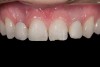

Fig 2. After orthodontic alignment of teeth and bleaching. Note alveolar deficiency in right lateral incisor site and diminutive left lateral incisor.

Figure 2

After 2 years of orthodontics, the appliances were removed, and his tooth coloration was improved using carbamide peroxide bleaching (Figure 2). Because some form of provisional needed to be placed until he was finished growing, a double-wing metal resin-bonded bridge was chosen. As discussed earlier, this is the ideal transitional prosthesis for patients that have congenitally missing maxillary lateral incisors. The benefits of this type of prosthesis include its ability to be removed and rebonded during the surgical phase of treatment and its ability to retain the roots in their proper position after orthodontic treatment.16 The final plan for the patient was to increase the width of the central and the maxillary left lateral incisor, utilizing porcelain laminate veneers to achieve the appropriate width/length ratio of 80%. A wax-up was created to idealize tooth size, a putty matrix was made from the wax-up to facilitate bonding of the incisors, and a non-precious, double-wing metal resin-bonded bridge was fabricated for lateral incisor replacement.